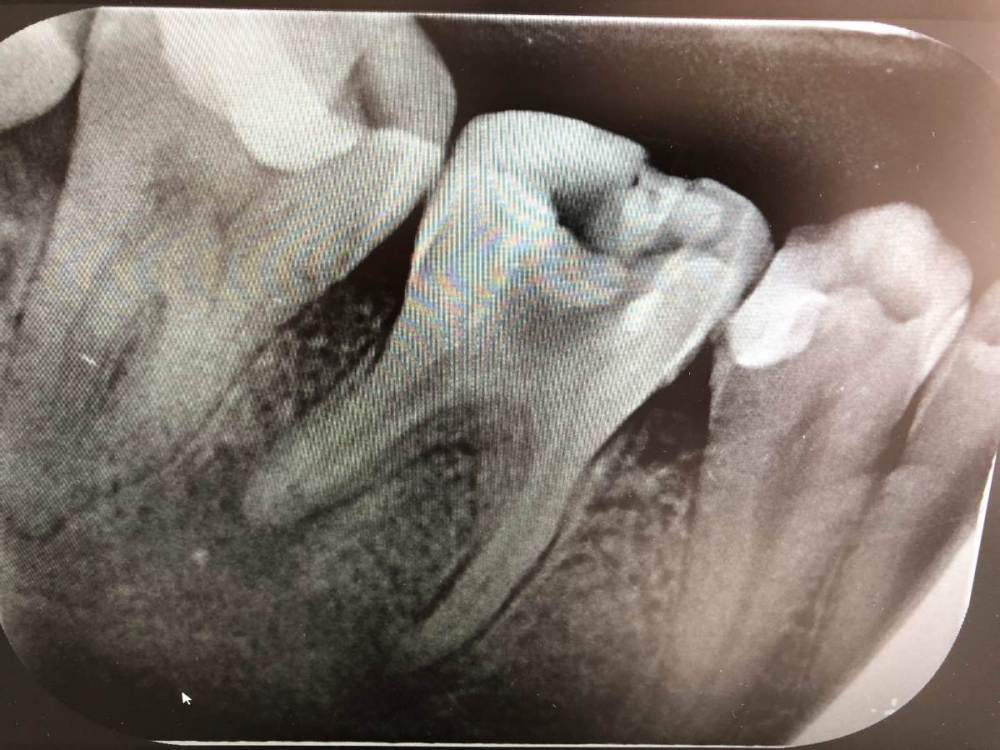

Samuel16 Опубликовано 8 августа, 2021 Поделиться Опубликовано 8 августа, 2021 Здравствуйте! Год назад я недолечил периодонтит из за вмешательства коронавируса. Я около года ходил со временной пломбой (в каналах был кальций), и зуб никак не тревожил. Когда я пришел его долечивать, мне положили лекарство в каналы и зуб начал болеть. Спустя месяц, мне уже собирались пломбировать каналы но внезапно пошла кровь. После этого, произошло что-то странное... Мне положили другое лекарство, и на этот раз провели бормашинкой по каналам. И после этого они будто заблокировались. Спустя день я обратился с сильной болью к стоматологу и был уверен, что как мне снимут пломбу и уберут лекарство то будет облегчение (как было до этого), но этого не случилось. Стоматолог сказал что каналы чистые, все должно быть нормально. Вообщем по нему я понял что он не понимает что произошло. Проблемный канал в котором постоянно была кровь был чистый в этот раз. Я чувствовал что очаг воспаления не может найти выход, у меня болел подбородок, и была сильная распирающая боль, и я был готов удалять зуб. Под обезболивающими я начал ходить на консультацию к другим стоматологам которые ничего конкретного не могли сказать. В последней клинике где я был, сказали что ничего удалять не надо, и что бы я несколько дней полоскал содовым раствором. Я начал полоскать. После несколько дней, каналы каким-то чудом открылись и оттуда пошла кровь, и действительно пошло облегчение. Но теперь из зуба идут довольно обильные, желтые выделения. Спустя неделю, мне сделали новый рентген снимок и сказали удалять зуб, а другой стоматолог сказал что по снимку мало что ясно и надо сделать КТ. Я сделал КТ и жду приема в понедельник... Я постарался выбрать момент на КТ где больше всего видна проблема. Ссылка на полное КТ - https://mega.nz/file/oQY3CazZ#4mVb3-ZUR_rZd5xl4FZqGt3hALHRQIItwfwuPb-5k7Q Смотрится все безнадежно... Но может, есть еще какой- то шанс на спасение зуба? Ссылка на комментарий

Samuel16 Опубликовано 8 августа, 2021 Автор Поделиться Опубликовано 8 августа, 2021 Также, прикладываю рентген снимок сделанный 28 июня. Ссылка на комментарий